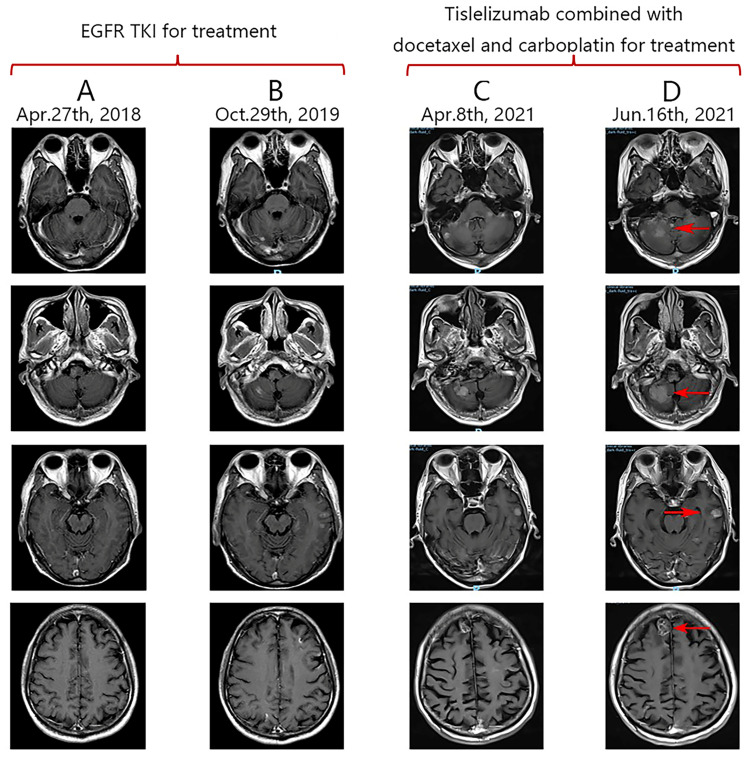

Lung adenocarcinoma (ADC) harboring epidermal growth factor receptor (EGFR) mutations rarely transforms into squamous cell carcinoma (SCC) following resistance to targeted therapy. Here, we present a case of EGFR-positive ADC that transformed into EGFR-negative SCC after developing resistance to EGFR tyrosine kinase inhibitors (TKIs). The patient experienced progressive disease after one cycle of chemotherapy and subsequently underwent five courses of tislelizumab combined with chemotherapy. Although the primary tumor showed a partial response to this combined regimen, intracranial metastases continued to progress, ultimately leading to the patient's death. Notably, the patient survived for 8 months after SCC transformation with immuno-chemotherapy, a significantly longer duration than the previously reported median survival of 3.5 months. This case underscores the occurrence of genomic instability, histological transformation, and dissociated response (DR) following treatment with EGFR-TKIs in EGFR-positive lung ADC. We hypothesize that these phenomena may be driven by tumor heterogeneity and the dynamic variability within the tumor microenvironment (TME).